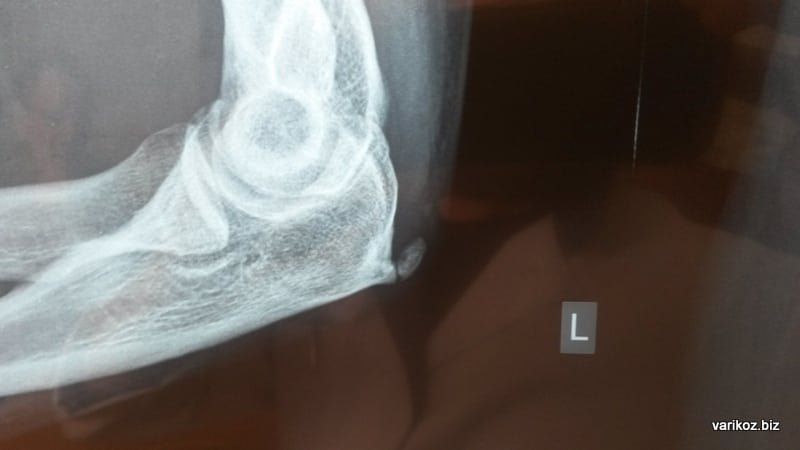

В большинстве случаев диагноз «латеральный эпикондилит» выставляют на основании клинической картины болезни. Если у врача есть сомнения, он проводит тест с подъемом стула и/или тест кофейной чашки. Для оценки состояния сухожилия пациенту могут выполнять ультразвуковой исследование (УЗИ).

Заболевание у лиц с деформирующим остеоартрозом

Считается, что болезнь теннисиста развивается из-за частых сгибаний/разгибаний руки в локтевом суставе. Однако к дегенеративно-дистрофическим изменениям сухожилий нередко приводит длительнотекущий деформирующий остеоартроз. По статистике, характерные признаки эпикондилита выявляют у 75-80% больных с артрозом локтевого сустава.

При ультразвуковом исследовании у таких пациентов наблюдается нечеткая визуализация сухожилий. При более детальном рассмотрении в них обнаруживают ан- и гипоэхогенные участки. В мягких тканях выявляют внесухожильные кальцификаты, а в кортикальном слое кости – слабовыраженные признаки дегенеративных изменений. У некоторых больных также визуализируются остеофиты.